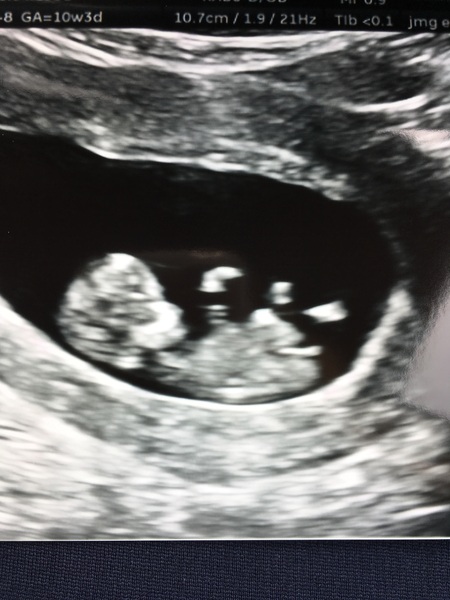

I’m mad but just had another early scan Blush I have been unwell since last week and got myself in a bit of a tizz about it so have been worrying but baby is all ok Smile Measuring correct and heartbeat 176 bpm.

Looks like a baby now amazing how much it has changed since 2 weeks ago.

Oh my God @wineandchoccy that is an great scan! So very clearly a baby, it's amazing how quickly they grow. Hope it's reassured you. :)

@wineandchoccy it is, at the same time I feel bad for being negative when I'm so happy to be pregnant again, but it's normal to feel both at once I think. Damn these uncontrollable street odours! Amazing scan though, those little limbs, wow.

@Wineandchoccy OMG that scan is amazing! Proper little person! Can't wait for my dating scan in a couple of weeks, remember it being so clear.